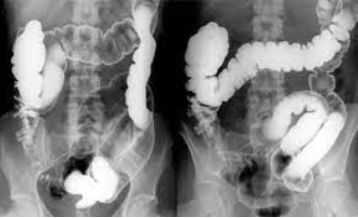

Figura 3: Série de posições no enema opaco. Fonte: Radiopaedia

Figura 4: Série de posições no enema opaco. Fonte: Radiopaedia

Documentação Mínima

- Abdome simples pré-exame

- Imagens em AP, PA, RAO, LAO e perfil

- Compressão manual para detalhamento mucoso

- Abdome simples pós-esvaziamento

- Confirmação de limpeza completa